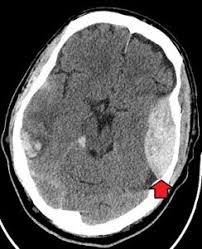

Aceste tipuri de hematoame dau o mortalitate ridicată (90%, chiar dacă sunt operate).